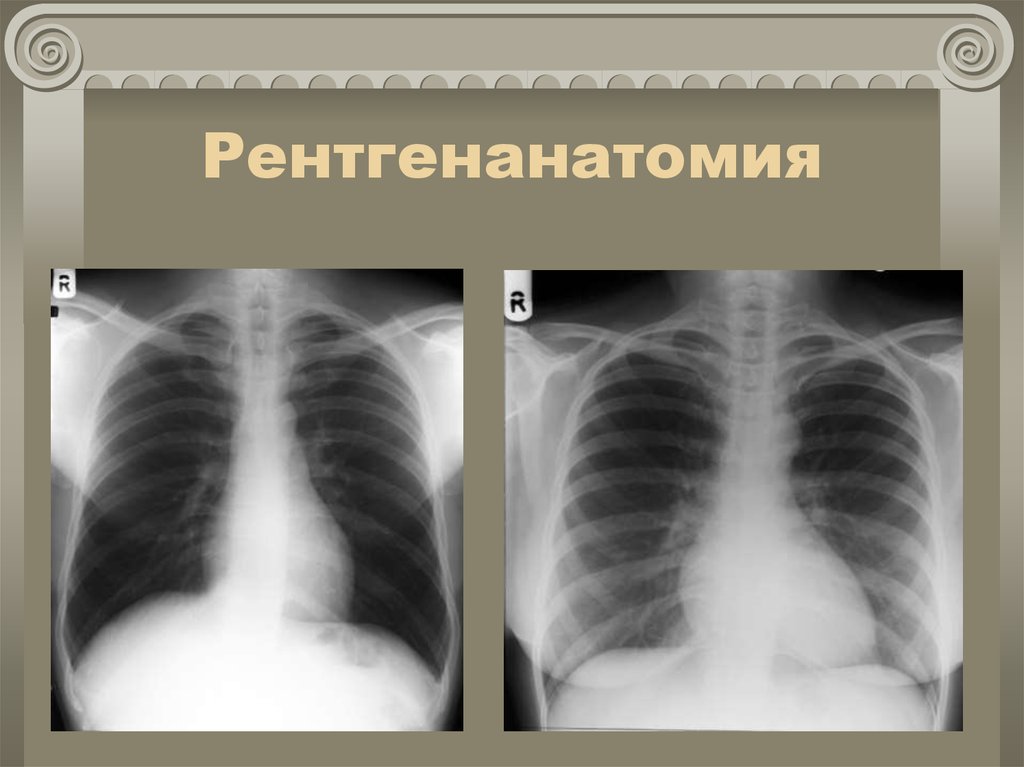

Рентгенанатомия